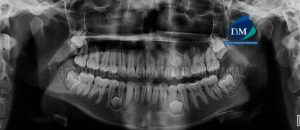

Paciente masculino de 64 años acude al Instituto de Diagnóstico Maxilofacial para la evaluación imagenológica de control. A la evaluación de la radiografía panorámica se